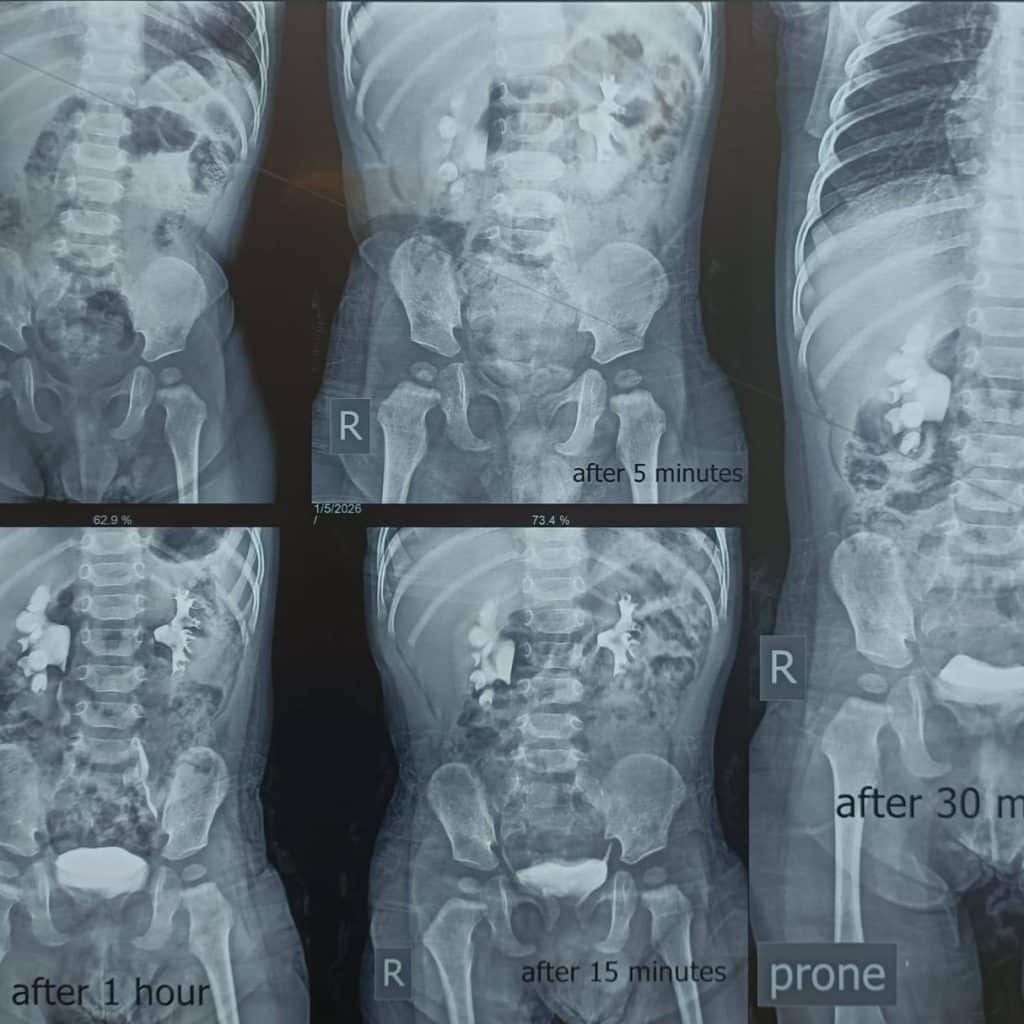

“أجرينا بفضل الله تعالى عمليات ناجحة لتصحيح تشوهات خلقية لدى ثلاثة أطفال كانوا يعانون من انسداد في كلا الحالبين، ما أدى إلى توسع في الكليتين وتسبب بحالة من عدم الارتياح والبكاء المستمر.”

“تراوحت أعمار الأطفال بين ستة أشهر وسنة وشهرين، وقد تزامن أن كل طفل منهم كان يعاني من درجتين مختلفتين من الانسداد؛ انسداد متوسط في أحد الحالبين، وانسداد شديد في الحالب الآخر.”

“تم التعامل مع الانسداد الشديد من خلال إجراء عملية تجميل حوض الكلية لإعادة تصحيح مسار البول، فيما عولج الانسداد المتوسط بواسطة الفتح الناظوري للحالب، وهو إجراء دقيق يساعد على إعادة انسيابية جريان البول.”

“الحمد لله، تكللت العمليات بالنجاح، وتمت استعادة عمل الجهاز البولي بصورة طبيعية، وغادر الأطفال المستشفى وهم في أتم الصحة والعافية.”